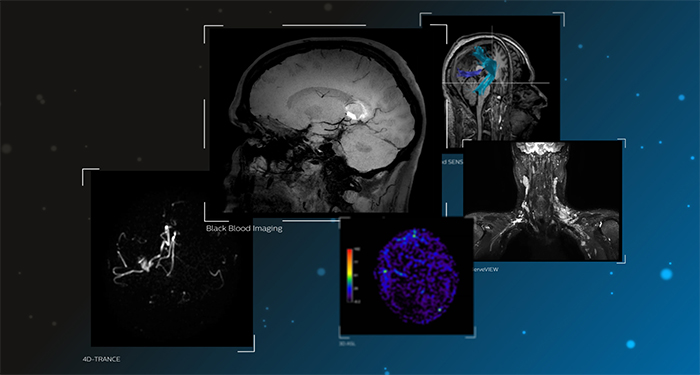

Improvements in clinical MR Neuro imaging

Advanced Neuro MR applications

Elevate Neuro diagnostics

Discover our neuro applications